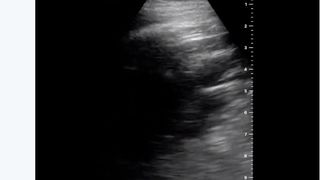

Medicul a arătat și cum i-a afectat temutul virus plămânii în numai câteva zile, dar și de decizie a luat atunci când a aflat că este infectat.

În plus, pentru a arăta cât de gravă este situația, medicul Chen a postat și footgrafii ale plămânilor săi.